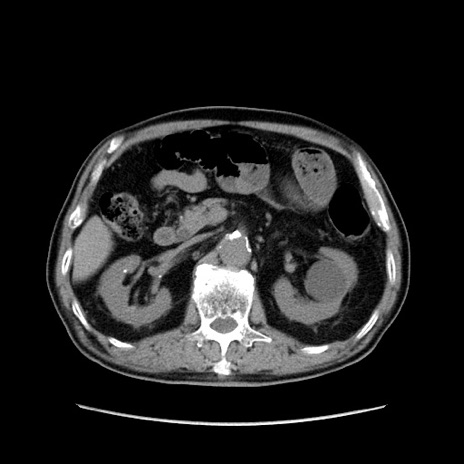

症例24(横断像)

【症例】80歳代男性

【主訴】左側腹部痛、嘔吐

【現病歴】本日早朝より左腹部に痛みあり。昼頃嘔吐認めたため、救急要請。

【既往歴】直腸癌(Mile手術)、胆摘

【身体所見】意識清明、BT 35.9℃、BP 221/93mmHg、SpO2 97%(RA) 、腹部:左ストーマ周囲に限局性の腹部膨隆あり。 膨隆部自発痛・圧痛あり・軟。

【データ】WBC 7700、CRP 0.09